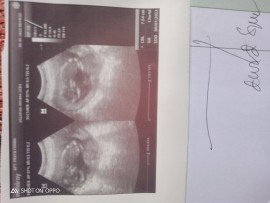

Usg di usia kandungan 13w4d

Assalamualaikum bund, Alhamdulillah hari saya sudah melakukan USG,dan Alhamdulillah kata dokter bayinya sehat dan djj nya sudah terdengar, menurut bunda nih yang sudah banyak berpengalaman apakah bayi saya sehat? Semoga kita semua di berikan kesehatan dan jga debatnya amin!!